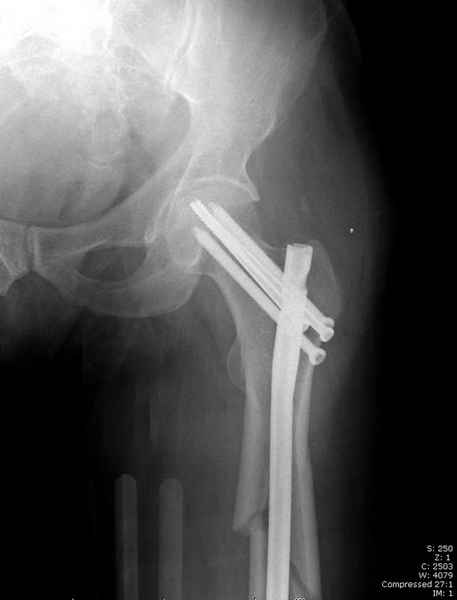

Среди русскоговорящих коллег Ортофорум стал одним из мест, где многие из нас черпают знания для решения своих ежедневных проблем в виде практических советов и обмена опытом. Кроме таких советов, Ортофорум стал источником новых познаний среди ортопедов, особенно по редко встречающимся состояниям в ортопедии. Продолжая традицию, я хотел бы представить редко встречающий случай перелома бедра у больного с гемофилией. Больному 42, гемофилия типа А, из истории упал с высоты около 1,5 метра, переправлен из другой больницы. По происхождению мексиканец, 10 лет назад по поводу артроза пр. коленного сустава в Мексике сделано протезирование, которое закончилось ампутацией выше коленного сустава. При поступлении бедро напряженное, сосудистых и неврологических расстройств нет. На рентгенограмме оскольчатый перелом бедра с вовлечением проксимальной спирали в шейку бедра. Хотели бы знать тактику ведения подобных больных и на что надо обратить внимание? Djoldas Kuldjanov, MD Department of Orthopedic Surgery St. Louis University Medical Center

Учитывая, что случай ургентный, больной поступил вечером, не стали делать вытяжение и срочно провели операцию по фиксации перелома бедра антеградным штифтом Versa Nail от DePuy.

Для профилактики дальнейшего раскола в шейке предварительно во время проксимального рассверливания спереди и сзади провели временные спицы, которые в дальнейшем были заменены на шурупы (miss nail method)

Кровотечение удалось контролировать, и больной через пару дней выписан на амбулаторное лечение.